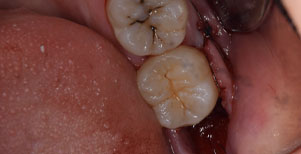

口腔内

半埋伏の親知らずでした。3糸縫合しました。